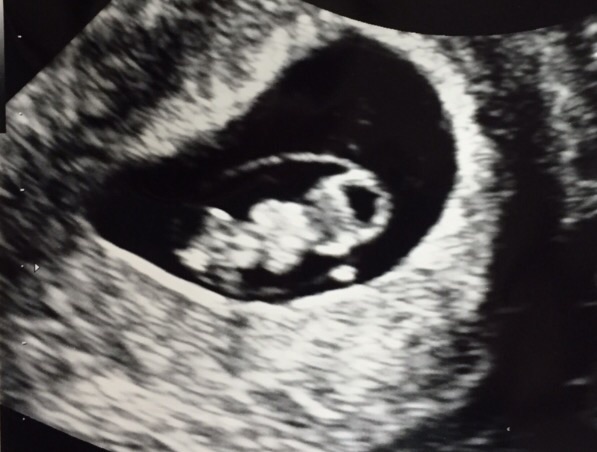

Just had our dating scan today! 8 weeks exactly! Here is cub's head & little arm/leg stumps! I have a cyst in an ovary but was told that should go away. This is our first!